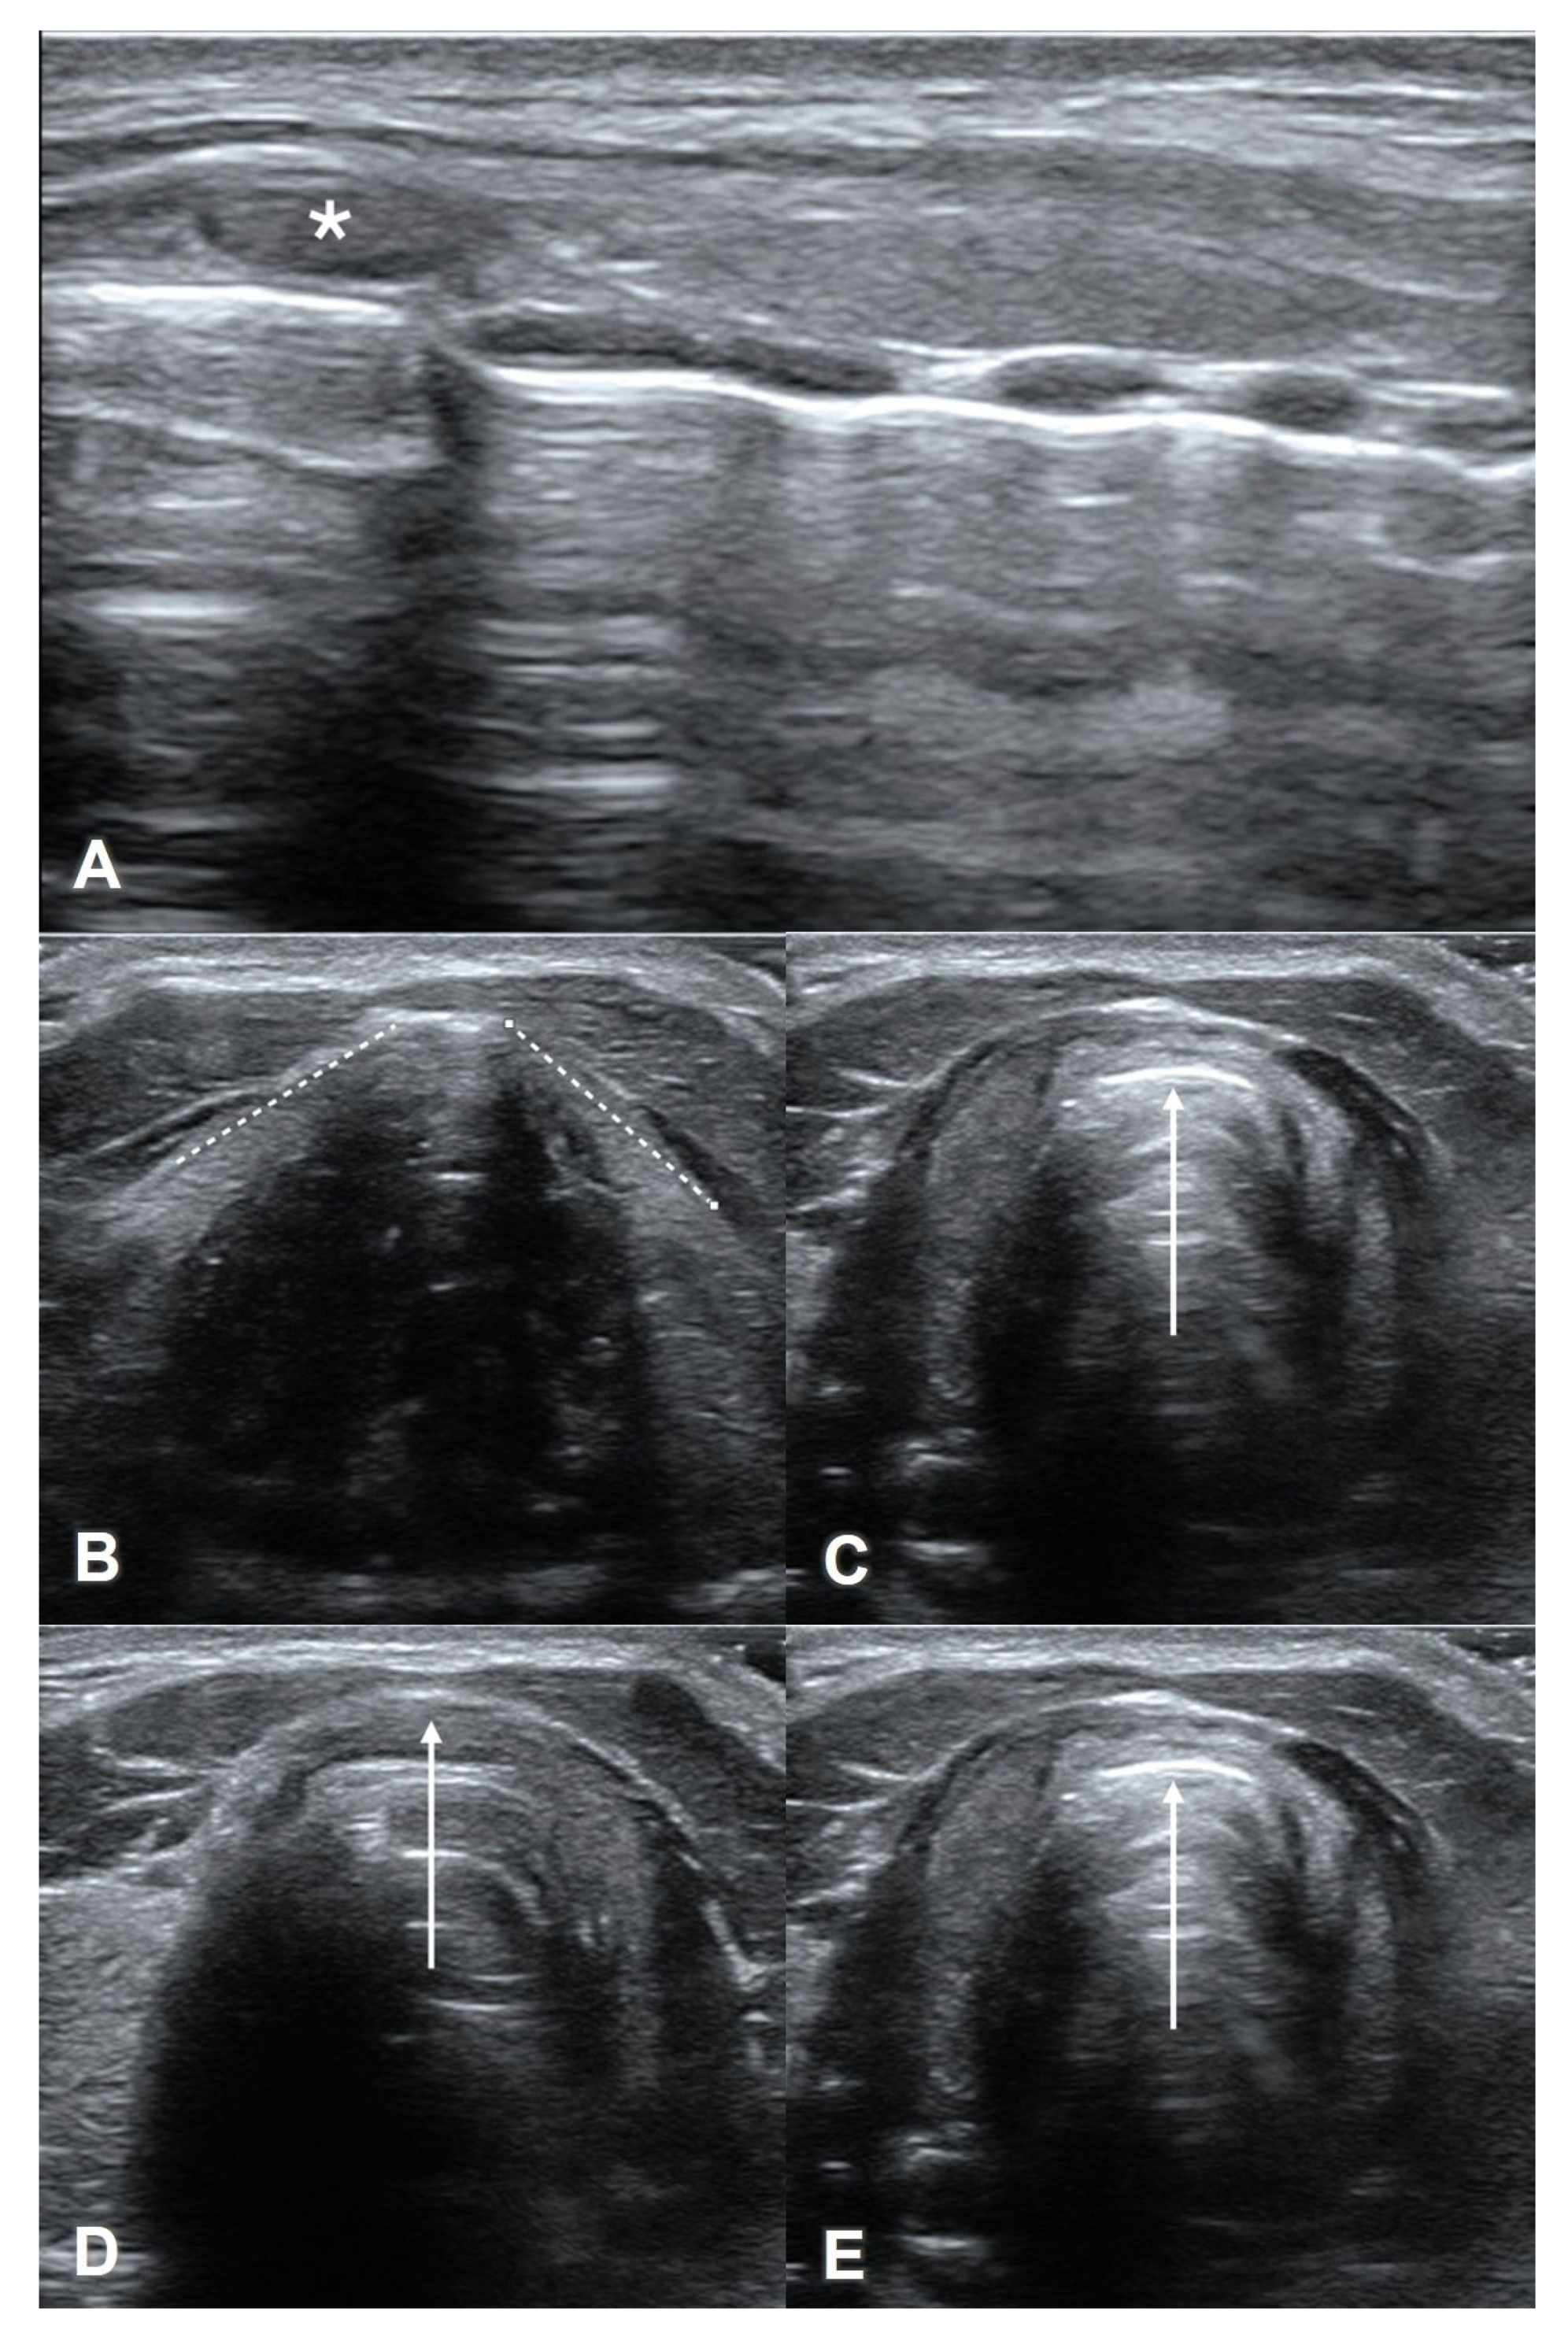

7. Assessment of Laryngeal Edema